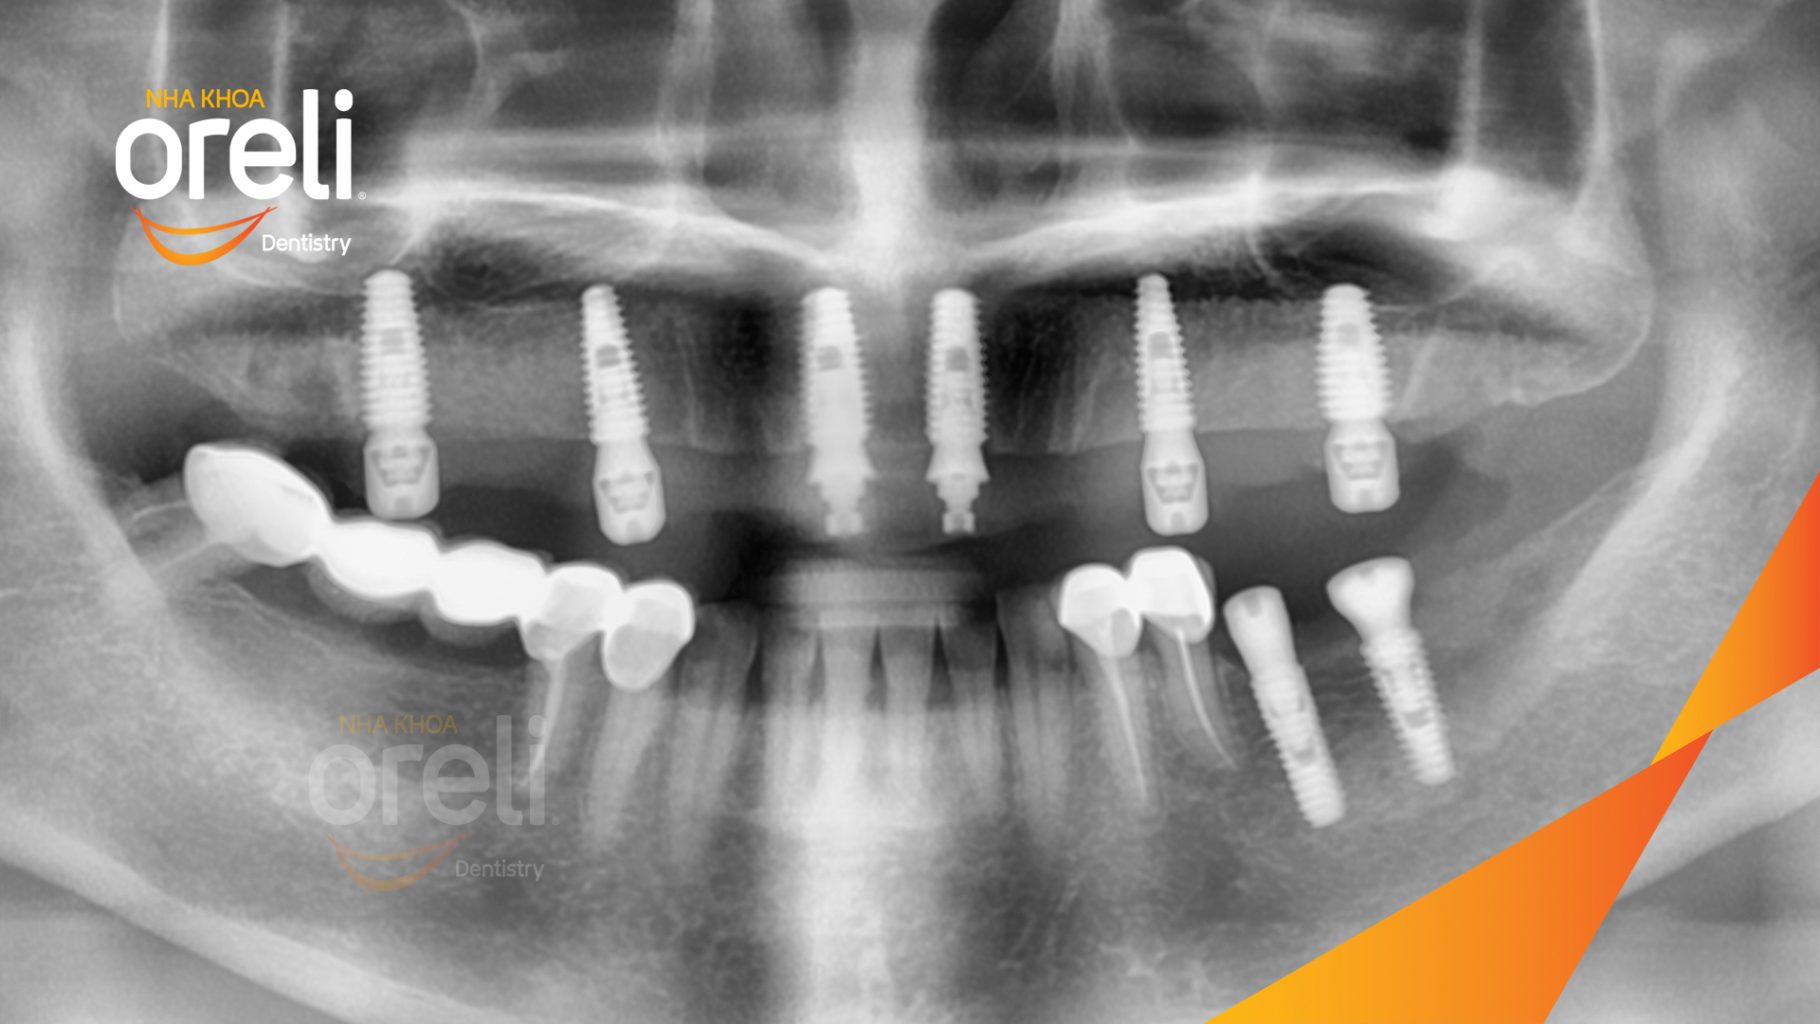

Tình trạng: Cầu răng sứ hàm trên lâu ngày gãy, viêm nướu, chân răng lung lay

Giải pháp: Cắt cầu răng sứ, nhổ răng, trồng răng implant

Kết quả: Phục hồi nụ cười tự nhiên và ăn nhai ổn định

Hình ảnh thực tế